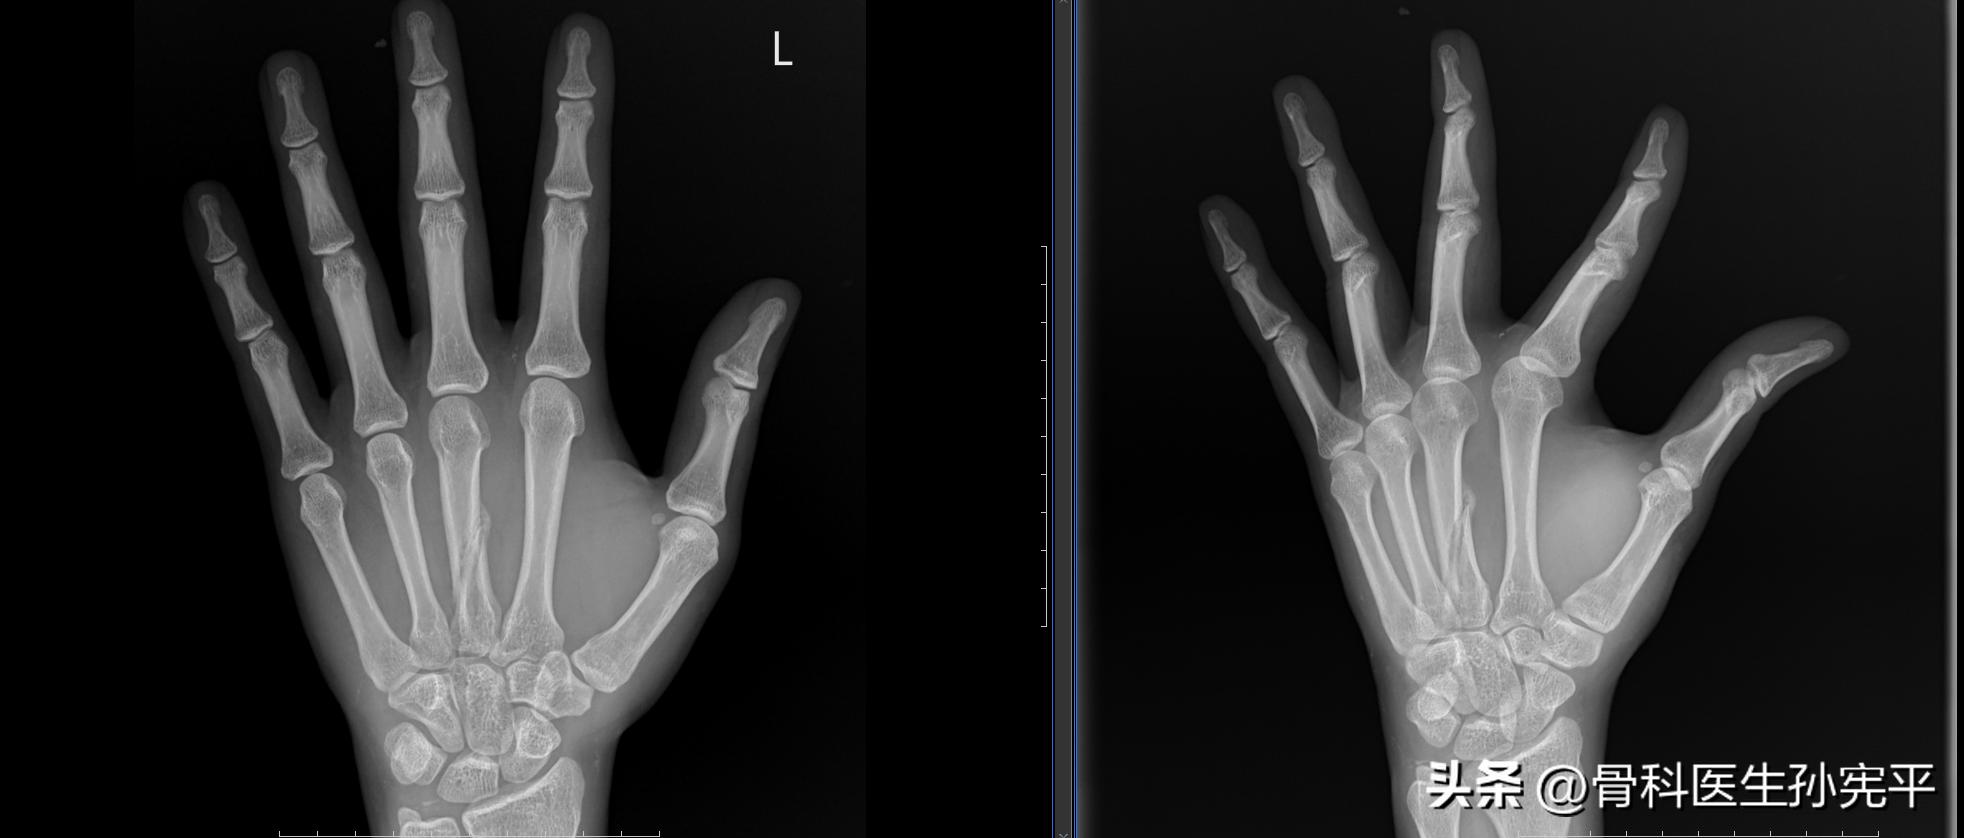

病例6:手部外伤6周

第3掌骨骨折

阅片可见左手第3掌骨骨质结构断裂,对位对线尚可,可见骨痂形成。